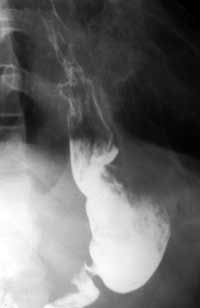

Рис. 4.  Патологические процессы, локализующиеся в верхних отделах желудка, в основном опухолевого генеза, завершаются выполнением проксимальной резекции желудка с формированием гастроэнтеростомы. Анастомоз формируется с оставшейся частью антрального отдела желудка или даже с препилорической зоной.

Культя желудка после субтотальной проксималъной резекции.